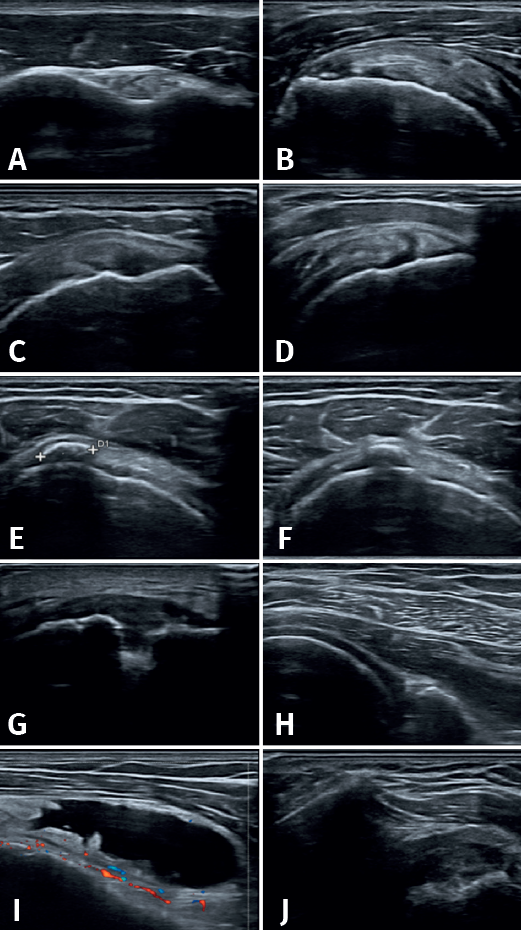

Se definieron los diagnósticos ecográficos de la siguiente manera (Figura 2): 1) tendinopatía: alteración de la ecoestructura fibrilar con alternancia de imágenes hiper- e hipoecogénicas a pesar de la corrección de la anisotropía con movimientos del traductor; 2) rotura tendinosa: imagen anecogénica intratendinosa que puede incluir a la rotura parcial (de tamaño variable con interrupción parcial de la ecoestructura normal), rotura parcial del espesor completo (la cual abarca el espesor tendinoso en su totalidad) y rotura completa (en la que se observa discontinuidad del tendón, generalmente presentándose adelgazado y en ocasiones con retracción tendinosa); 3) sinovitis: imagen anecogénica, peritendinosa o articular, de más de 2 mm de grosor proveniente de la membrana sinovial; 4) tendinopatía calcificante: imagen hiperecogénica sólida, única o múltiple, de tamaño variable, con o sin sombra posterior; y 5) bursitis: imagen anecogénica de más de 2 mm de espesor, entre el tendón del supraespinoso y el músculo deltoides o en el borde lateral del troquíter(22).